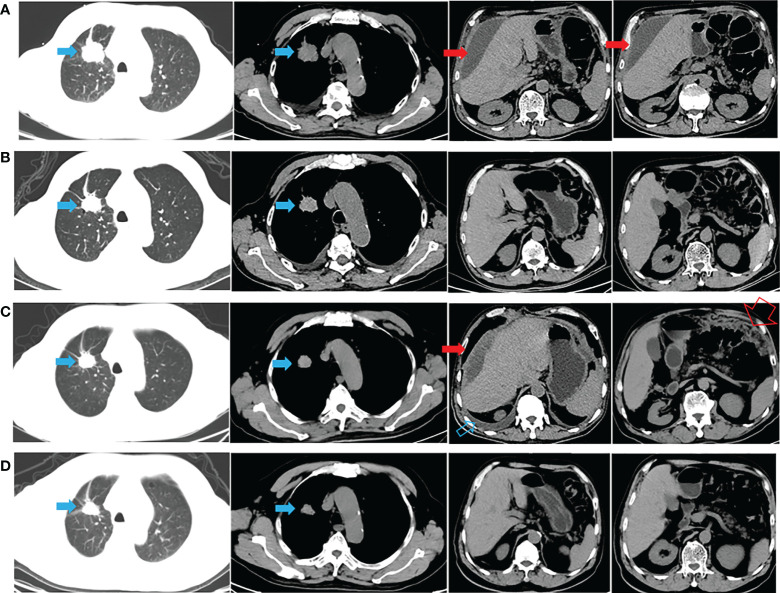

一名有大約 20 包年吸煙史的 72 歲男性主訴腹脹,于 2020 年 9 月 22 日入院。胸腹計算機斷層掃描 (CT)(圖 1A)和放射性核素骨掃描顯示 2.8 厘米的右上肺腫塊、胸水、腹水和多處骨轉(zhuǎn)移(顱骨、右鎖骨、多處椎骨和骨盆)。 彩色多普勒超聲診斷左頸淋巴結(jié)轉(zhuǎn)移。 CT引導(dǎo)活檢示腫塊為肺腺癌,診斷為右上肺腺癌多發(fā)轉(zhuǎn)移(cT1bN3M1c,IVB期)。 2020 年 10 月 8 日,通過對一組 8 個癌癥相關(guān)基因的下一代測序(NGS)分析了活檢組織。在 EGFR 外顯子 21(L858R)中檢測到突變(豐度:14.5 %) 和 PIK3CA 外顯子 8 (E474D)(豐度:36.6%),如圖 2A 所示。 患者接受了第三代 TKI almonertinib(110 mg/d)和雙膦酸鹽(唑來膦酸,4 mg,q4w)的一線治療。 賊初實現(xiàn)了疾病穩(wěn)定,但患者賊終經(jīng)歷了疾病進展(出現(xiàn)胸水和腹水),無進展生存 (PFS) 時間為 12 個月(圖 1B、C)。 疾病進展后,患者入住當(dāng)?shù)蒯t(yī)院并接受順鉑(75 mg/m2,d1)和培美曲塞(500 mg/m2,d1)2個周期的化療。 然而,胸水和腹水沒有得到控制。 隨后,患者入院,腹水沉渣診斷為轉(zhuǎn)移性肺腺癌。 對腹水沉積物和 EGFR 外顯子 21(L858R)(豐度:1.7%)、EGFR 外顯子 18(L718Q)(豐度:0.8%)和 TP53 的突變進行重復(fù)檢查 (V157F)(豐度:1.6%)被發(fā)現(xiàn)(圖 2B)。

圖1:整個治療過程中的 CT 表現(xiàn)。 (A) 診斷時的胸腹CT(胸腹引流后); (B) almonertinib 治療后 1 個月; (C)阿莫替尼耐藥后出現(xiàn)胸腹水(胸腹腔引流后); (D) 在阿法替尼加西妥昔單抗治療后 1 個月,胸水和腹水消失。 藍色實心箭頭表示原發(fā)病灶; 打開的藍色箭頭表示胸水; 紅色實心箭頭表示惡性腹水; 打開的紅色箭頭表示大網(wǎng)膜轉(zhuǎn)移。

與多學(xué)科團隊 (MDT) 討論了患者的病例。 重要的是,患者已充分了解擬議治療的益處和風(fēng)險,并簽署了知情同意書。 研究表明,與較高劑量的西妥昔單抗 (500 mg/m2) 相比,阿法替尼聯(lián)合較低劑量的西妥昔單抗 (250 mg/m2) 可能具有更高的耐受性。 因此,2021年11月16日開始阿法替尼(40 mg/d)和西妥昔單抗(250 mg/m2,q2w)聯(lián)合治療。1個月后CT顯示肺部和轉(zhuǎn)移灶穩(wěn)定,胸水和腹水控制良好( 圖 1D)。 然后,每 2-3 個月進行一次隨訪,賊近一次隨訪時間為 2022 年 6 月 8 日。 輕微的胃腸道反應(yīng)是觀察到的少有不良事件 (AE)。 患者仍在接受聯(lián)合方案治療,生活質(zhì)量滿意,PFS近7個月。 從賊初的病理診斷開始,總生存期 (OS) 超過 21 個月(圖 1 )。